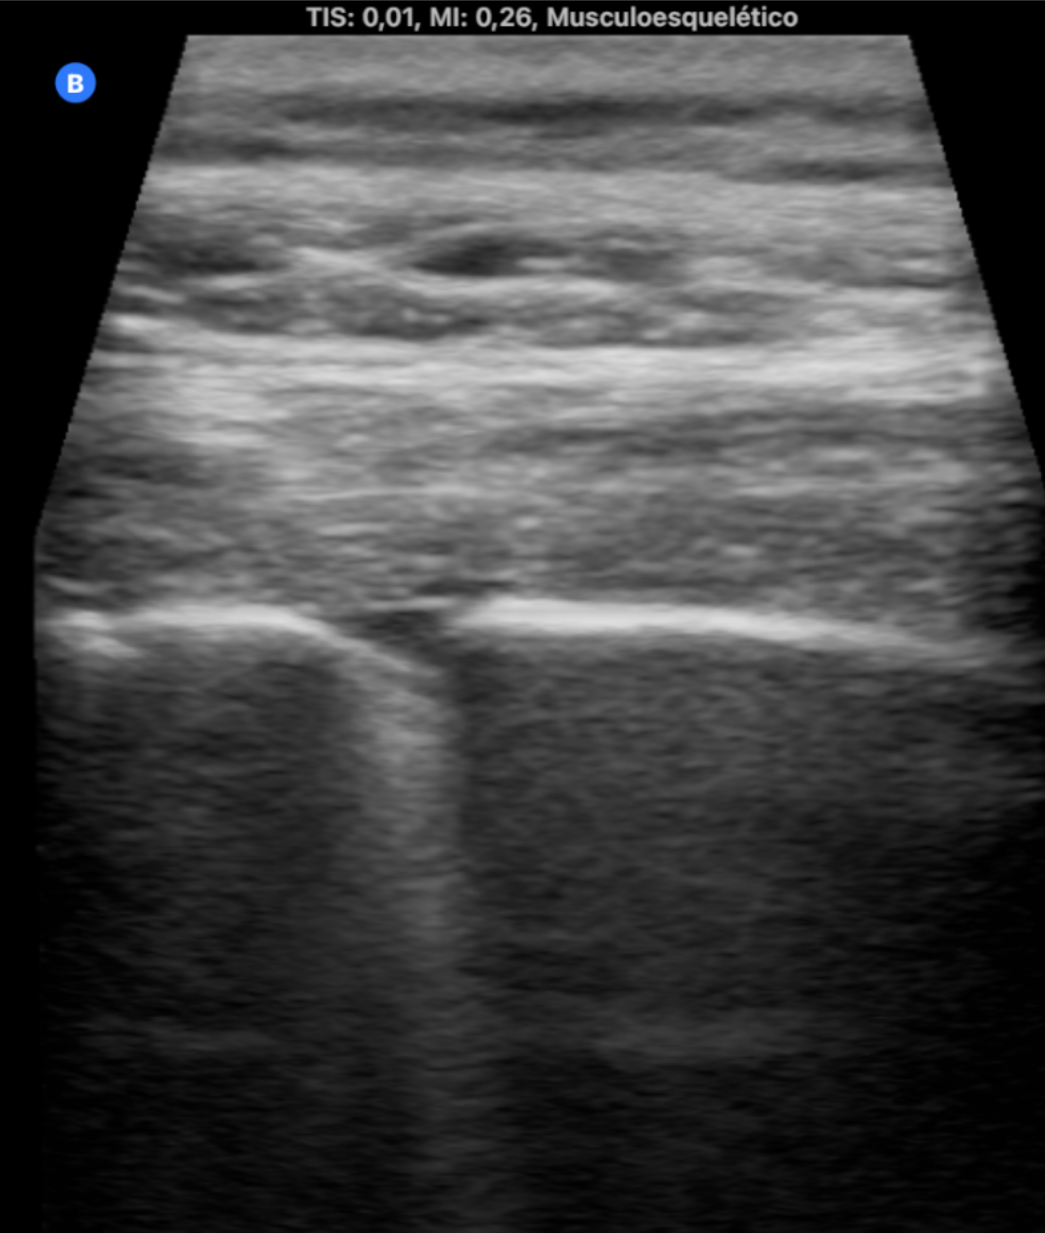

La medicina de familia no tiene horarios ni fronteras. Durante el último año, hemos incorporado el ecógrafo ultraportátil a nuestra vida diaria no como un recurso improvisado, sino como una herramienta integrada en nuestra práctica diaria capaz de dar respuesta inmediata a demandas clínicas surgidas en el entorno comunitario. En este contexto, han surgido situaciones en las que la ecografía ha sido determinante: diagnóstico de neumonías en domicilio, confirmación de roturas fibrilares tras actividad deportiva, fractura costal, valoración de hematomas y complicaciones postquirúrgicas, e incluso la identificación de una enfermedad pulmonar intersticial. Todo ello fuera del centro de salud, sin acceso a historia clínica ni a pruebas complementarias, únicamente con la sonda, la experiencia clínica… y una gran responsabilidad emocional. Estas situaciones generan un desafío distinto: no hay anonimato, y la confianza.

La ecografía ultraportátil amplía la capacidad resolutiva del médico de familia más allá de la consulta. Con herramientas sencillas y bien utilizadas, la Atención Primaria puede acercarse aún más a la población, ofrecer respuestas rápidas y mantener su esencia profundamente humana.

Cualquier médico de familia con formación básica en ecografía y acceso a un ecógrafo portátil puede implementar esta práctica. Especialmente útil en zonas rurales, en atención domiciliaria o en situaciones de difícil acceso al sistema. Reduce derivaciones innecesarias y mejora el acceso al diagnóstico precoz.